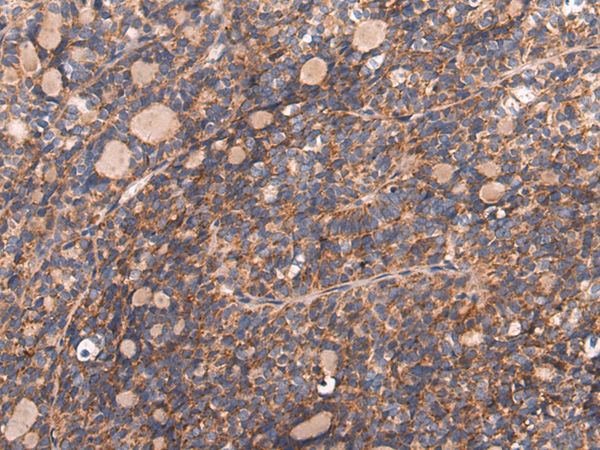

分类: 科研抗体货号: P10292别名: NP22; NP24; NP25应用: IHC反应种属: Human, Mouse, Rat